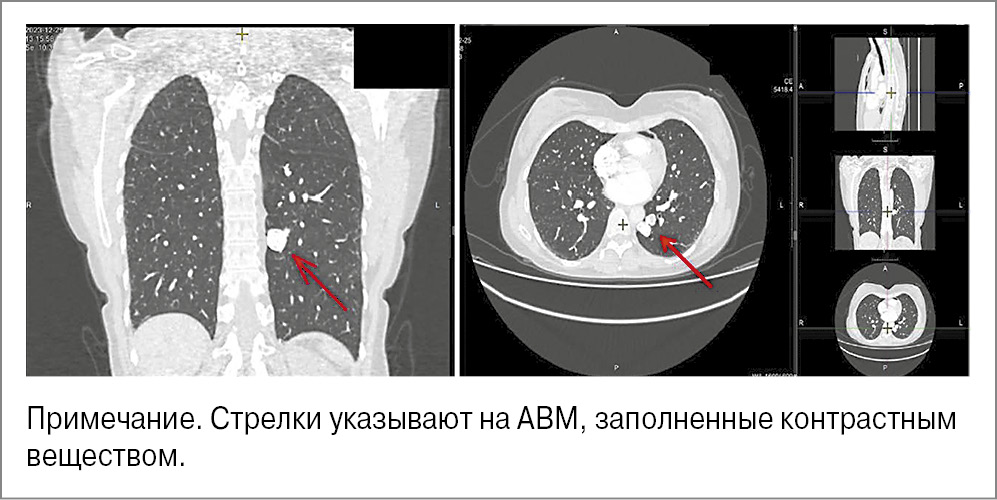

Выявленная ЛГ требовала выполнения КТ ОГК с внутривенным контрастированием. Заключение: прямых признаков тромбоэмболии легочной артерии (ТЭЛА) не выявлено. Округлые структуры нижних долей обоих легких, вероятно, сосудистого генеза (АВМ?). Состояние после эмболизации АВМ в нижней доле слева и резекции SII справа (рис. 3).

Рис. 3. КТ ОГК пациентки.